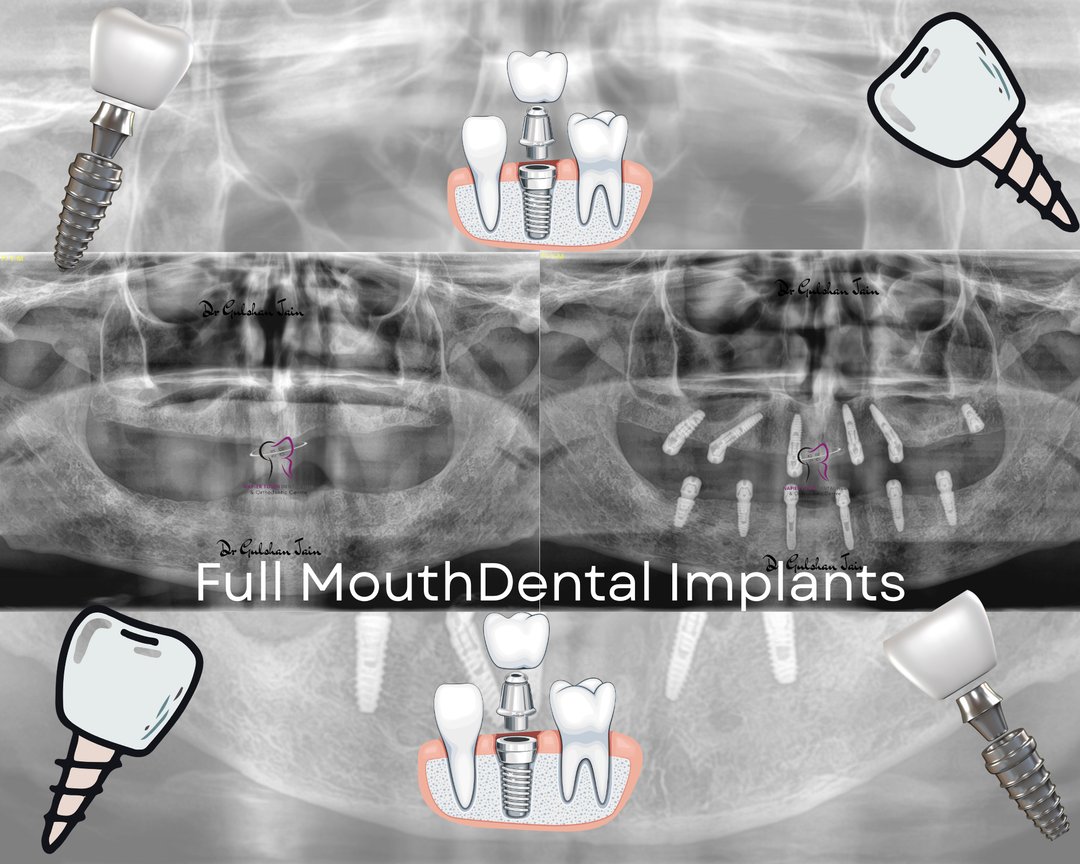

Welcome to our gallery

See how our company transforms ideas into reality. This gallery is a visual testament to our work and achievements.